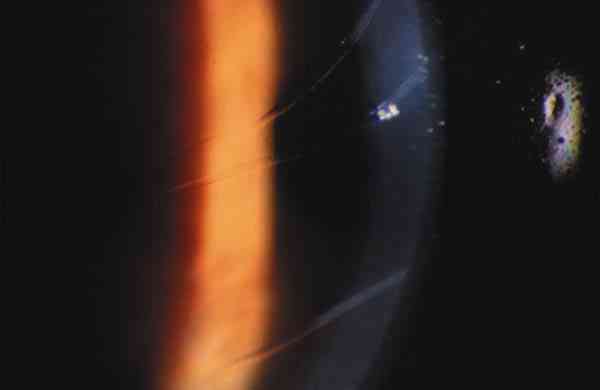

2. Exploración de segmento anterior: debe realizarse con lámpara de hendidura si es posible, y si no, con una linterna y una lupa. Hay que explorar la córnea valorando el grado de transparencia, la existencia de estrías y/o roturas de la capa de Descemet y el grado de edema. En fases más avanzadas la córnea puede tener un aspecto opalescente o puede mostrar zonas opacas en las áreas correspondientes a roturas de la Descemet. Hay que identificar la presencia de alteraciones asociadas en iris o córnea. Esta exploración tiene también valor pronóstico ya que permite valorar el abordaje quirúrgico que podrá realizarse en función de la transparencia de medios (foto 1).

11f-01.jpg (4672 bytes)

Foto 1. Estrías de Haab.